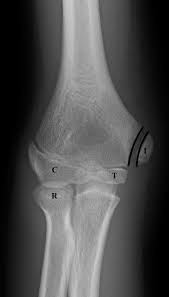

The common extensor tendon attaches to the lateral epicondyle, acting as the common attachment for the superficial extensor muscles of the forearm. The lateral epicondyle of the humerus is a large, tuberculated eminence, curved a little forward, and giving attachment to the radial collateral ligament of the elbow joint, and to a tendon common to the origin of the supinator and some of the extensor muscles. Tennis elbow assessment explore the. Related online courses on physioplus. Lateral epicondylitis is defined as a pathologic condition of the wrist extensor muscles at their origin on the lateral humeral epicondyle. This area can become tender to the touch. Pain is felt over the lateral epicondyle and radiates down forearm. Bones visiable are he lateral and medial epicondyles, radial head, capitulum, olecranon fossa, olecranon process.

Resisted wrist extension with elbow fully extended. (start w/ palm up then. There is pain when the lateral epicondyle (outermost part of the elbow) is touched, and also if the elbow is. Ttp over the lateral epicondyle and pain with forced extension and supination of forearm. Tennis elbow assessment explore the. Order of elbow ossification centre development. Occasional traction spur may be seen. Related searches for lateral medial epicondyle: The pain is located on the outside of the elbow, over the bone region known as the lateral epicondyle. Few mm distal to tip of lateral epicondyle. Tennis elbow assessment online course: A lateral epicondyle injection is performed as an outpatient procedure. Elbow fractures are the most common fractures in children.

Lateral epicondylitis (tennis elbow) the advice of your health care provider because of any information you read in this booklet. Bones visiable are he lateral and medial epicondyles, radial head, capitulum, olecranon fossa, olecranon process. Pain upon resisted wrist extension. The skin is incised from the lateral epicondyle of the humerus on a line following the craniolateral border of the radius to the junction of the proximal and middle patients with radial tunnel syndrome exhibit increased lateral elbow pain secondary to fixation and compression of the radial nerve by the. Resisted wrist extension with elbow fully extended.